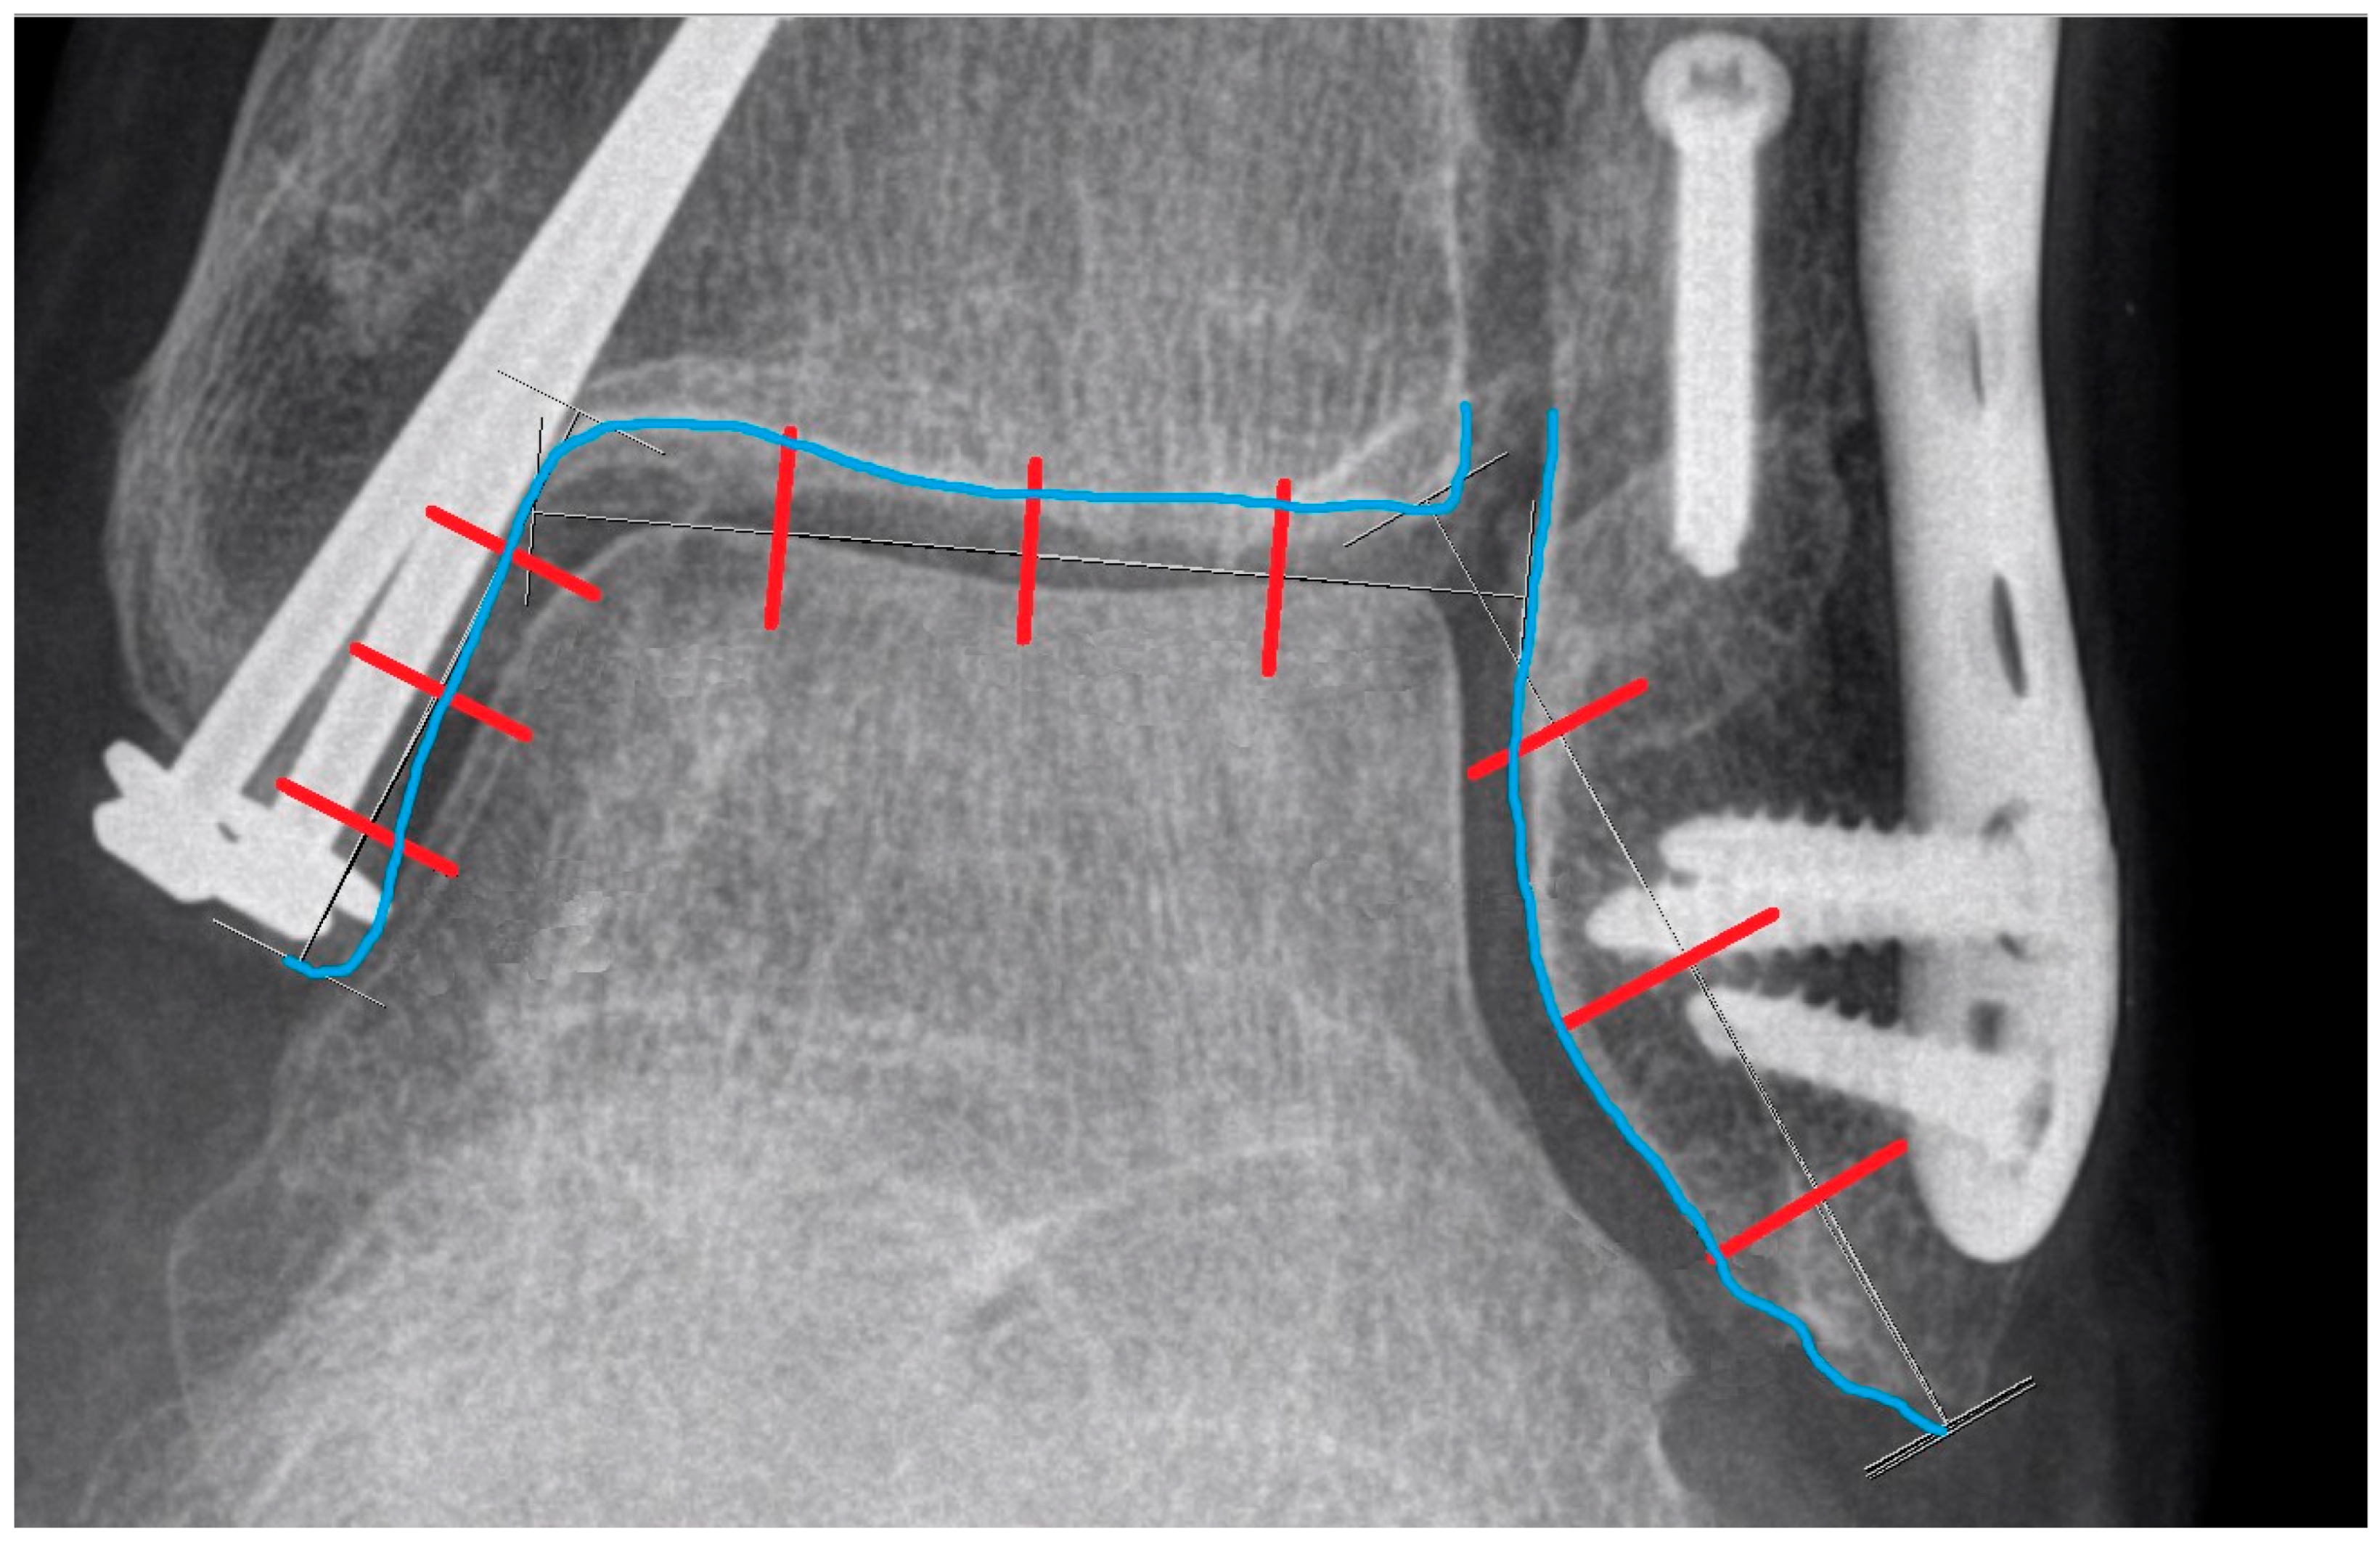

For all joint space measurements (1, 2, 3), equal intervals were utilized to enhance the repeatability of the calculations. Three proportional lines were employed to establish reference points for measuring the joint space:

Line X: drawn from the tip of the medial malleolus to the curve connecting the medial malleolus with the tibial plafond;

Line Y: drawn from the tip of the fibula to the most medial point of the tibial plafond;

Line Z: established by connecting the highest points of the talar bone and extending the line to make contact with the fibular and tibial cortex within the joint.

Lines X, Y, and Z are presented below (Figure 8).

Then, Lines X, Y, and Z were proportionally divided into four equal parts by three perpendicular lines, which were extended to intersect the contour of the tibial and fibular cortex, creating our points of reference (Figure 9).

Figure 9. The blue line represents the cortical contour of the tibia and fibula. The red lines divide the previously shown Lines X, Y, and Z into four equal parts. These red lines are extended perpendicularly and intersect with the blue contour, creating reference points for further measurements.